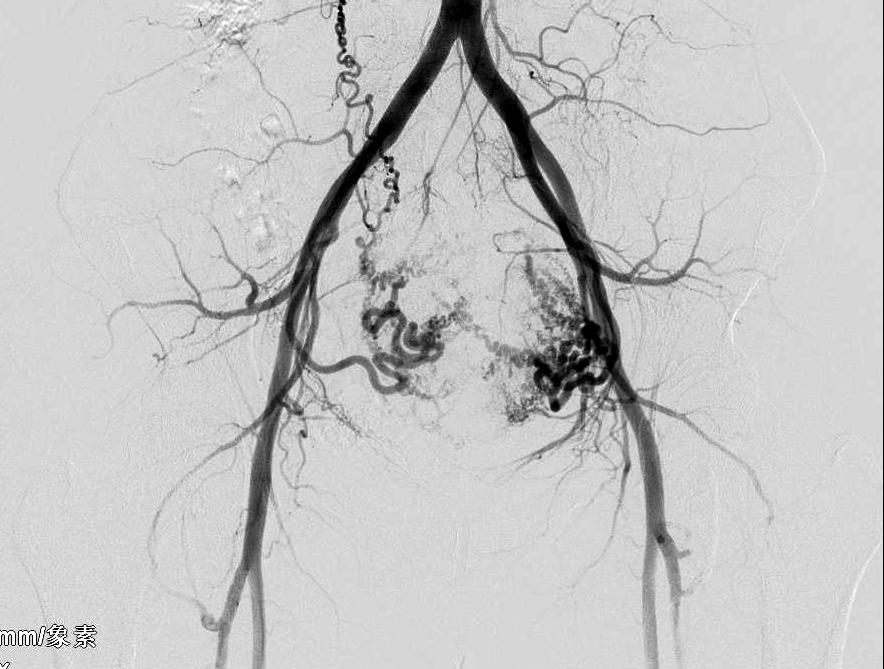

术前介入科主任李建国综合评估患者情况后,制订出个性化治疗方案。采用右侧桡动脉穿刺超选择双侧子宫动脉造影栓塞术,可避免传统股动脉穿刺术后制动24小时,给患者和护理人员带来不便,同时避免因卧床制动易形成下肢深静脉血栓的风险,但桡动脉到胸主动脉再到腹主动脉最终到盆腔子宫动脉,给手术操作者带来很大挑战。

8月16日早8时手术开始,在医护默契配合下,手术历时三十五分钟,异常供血的子宫动脉血管被全部封堵栓塞,手术成功,术后患者由护理人员搀扶走出手术室。